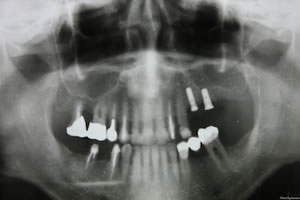

手術終了して、パントモ撮影、ネジが2本入ったのがおわかりでしょう。これから4,5ヶ月私の場合はきちんと正嫡するのを待つことになる。正嫡したらこのインプラントのとに歯の土台となるエクステンションをつけてそれに歯をかぶせる。それでやっと左の奥歯でものを噛めるようになるという流れ。下の写真は手術をして下さった麗奈先生、右と妹さん先生のお二人と記念撮影。術後も痛みはほとんどなく少し顔面の腫れはあるが反対側の歯で食事も問題無しです。ありがとうございました。あとは無事に私の骨と馴染んでくれるかどうかですね。 |